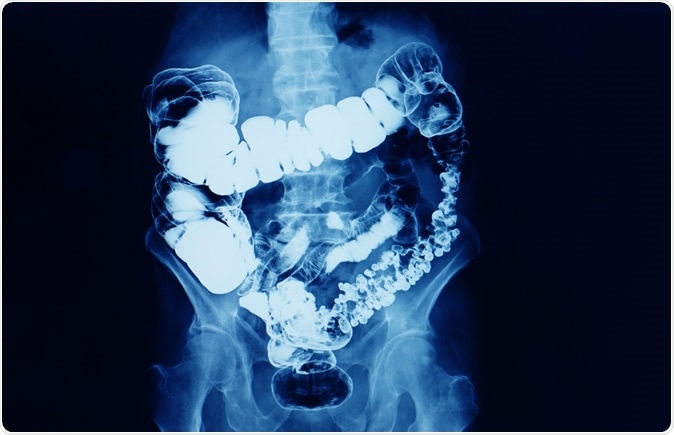

Barium enema x-ray showing contrast fill in most part of the large intestines such as transverse colon, sigmoid colon, and rectum. the patient has colon cancer. Image Credit: Yok_onepiece / Shutterstock